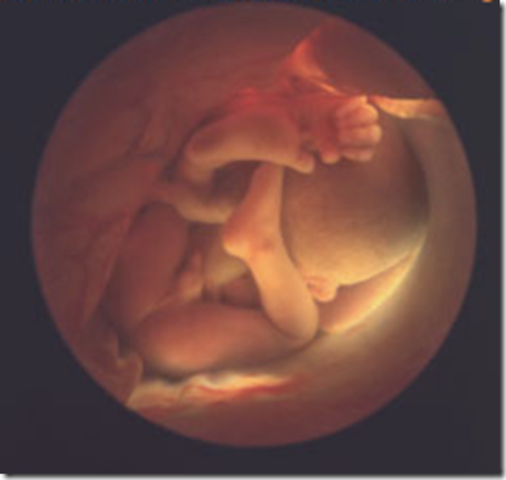

• week 32

week 32

By now, your baby weighs 3.75 pounds (pick up a large jicama) and is about 16.7 inches long, taking up a lot of space in your uterus. You're gaining about a pound a week and roughly half of that goes right to your baby